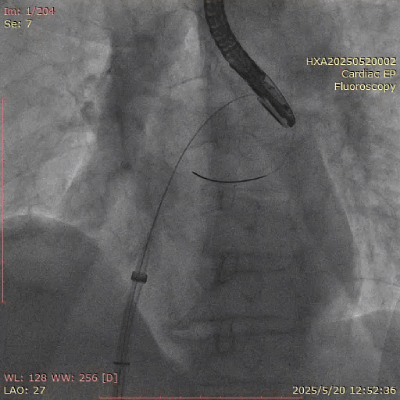

在经股静脉途径的TEER手术时,房间隔穿刺是一个很重要的基础步骤。有时候房间隔组织较韧较厚(多见于房间隔短穿刺位置需要靠后,或者外科房间隔修补术后),穿刺针通过之后要通过导引大鞘(GC)存在着较大困难,若强行推送大鞘可引起房间隔撕裂到左心房顶引起灾难性心包填塞。传统做法时使用外周球囊对房间隔进行扩张,但是不是每个导管室都常规配备外周球囊,且使用过大球囊仍可引起房间隔撕裂风险。我们提供了一种更简洁的方式,即使用导引鞘内芯和房间隔穿刺鞘两个管子(双管齐下)同时扩张房间隔穿刺口,再推送导引大鞘通过房间隔,无需额外器械,操作简单高效且安全(图1-4)。

图1. 房间隔穿刺处肥厚,GC难以通过房间隔